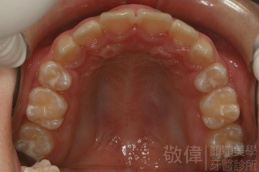

齒顏矯正/上顎暴牙且牙齒極度混亂

矯正後-右   矯正後-正   矯正後-左

矯正前-上   矯正前-下

<個案說明>

上顎暴牙且牙齒極度混亂,經由矯正之後,臉型大幅度改善,牙齒的排列更加的整齊健康。相較於之前眼神充滿精神,自信心展現無遺。